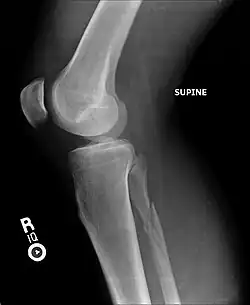

| Radiograph showing a Maisonneuve fracture of the proximal fibula | |

The Maisonneuve fracture is a spiral fracture of the proximal third of the fibula associated with a tear of the distal tibiofibular syndesmosis and the interosseous membrane. There is an associated fracture of the medial malleolus or rupture of the deep deltoid ligament of the ankle. This type of injury can be difficult to detect.[1][2]

Ankle radiographs are used to detect widening of the tibiofibular syndesmosis or medial clear space. The medial clear space is the area between the talus of the ankle and the medial malleolus. Damage to the deltoid ligament and syndesmotic ligaments result in mortise instability, causing the talus to laterally shift and widen the medial clear space.[4][12] A clinical study, conducted in 2006 and published in the Journal of Bone and Joint Surgery, found that the medial clear space size of a normal ankle and an injured ankle measured at 4 millimetres and 5.4 millimetres in length respectively.[11] To confirm diagnosis, full-leg radiographs are used to inspect for fractures of the proximal fibula and widening of the interosseous clear space (or tibiofibular clear space). The interosseous clear space is the area between the medial side of the fibula and lateral side of the tibia. A peer-reviewed study, published in Injury in 2004, found that an interosseous clear space greater than 10 millimetres indicates diastasis of the syndesmotic ligaments.[4]

X-ray, CT, or MRI scans can be used to diagnose the extent of the Maisonneuve fracture's damage and determine whether it is a simple or comminution fracture.[8] During diagnosis, a supination-external rotation pattern of injury may also be concluded if there is an isolated fracture of the posterior tubercle of the tibia.[9]